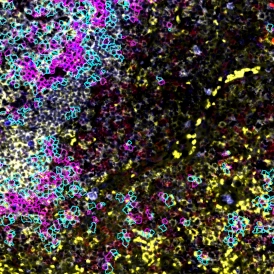

The IF 4 App provides single cell-based co-expression analysis for four IF markers. It segments cells into their nucleus, perinuclear area, and/or cytoplasm. Each segmented cell compartment is measured for up to 20 intensity, statistic, and morphometric parameters that can be displayed in and exported into scattergrams and histograms.

App Category 2

The IF Hi-Plex 50 App combines and analyses images of the same IF-stained tissue section, acquired up to 50 times with different markers. The App enables the detection of the cellular phenotypes of specific IF-stained cell populations. It segments cells into their nucleus, perinuclear area, and/or cytoplasm. Each segmented cell compartment is measured for up to 20 intensity, statistic, and morphometric parameters that can be displayed in and exported into scattergrams and histograms.

App Category 3